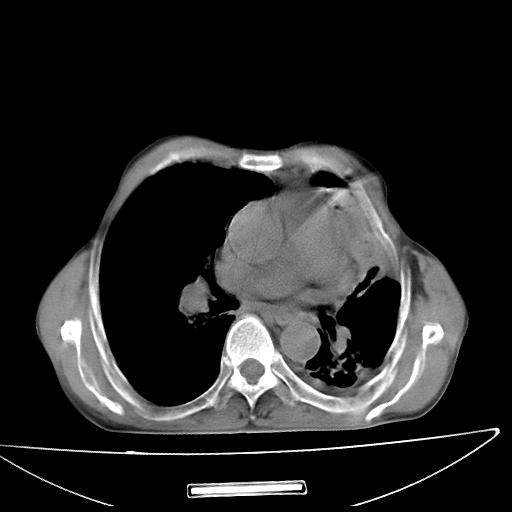

男  70岁,发烧咳嗽4天。盗汗,消瘦。无痰中带血丝,以前有肺tb病史,ct见,双肺tb,左侧胸廓塌陷,左胸膜肥厚粘连。纵隔移位,右侧胸腔积液,大家说说那个心影前左肺舌叶除了肺大炮还有炎症还是干酪性肺炎?有占位吗?我看纵隔淋巴结也大。

1)两肺继发性肺结核并左肺上叶肺不张,支气管扩张。2)双侧胸膜炎(胸膜增厚+少量胸腔积液)。

两肺继发性肺结核并感染,左肺上叶肺不张。建议ct增强。